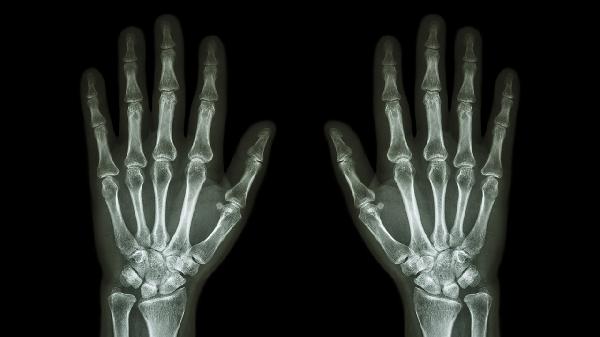

手指关节受到撞击、扭伤等外力作用可能导致局部软组织损伤或骨折,表现为突发肿胀疼痛伴活动受限。轻微外伤可通过冰敷缓解肿胀,48小时后改为热敷促进血液循环。若疼痛持续加重或出现关节畸形,需拍摄X线片排除骨折,必要时使用支具固定。

退行性骨关节炎常见于中老年人,晨起时关节僵硬感明显,活动后疼痛减轻但过度活动会加重。X线可见关节间隙狭窄、骨赘形成。可遵医嘱使用双氯芬酸钠缓释片、硫酸氨基葡萄糖胶囊等药物,配合关节腔注射玻璃酸钠改善症状。